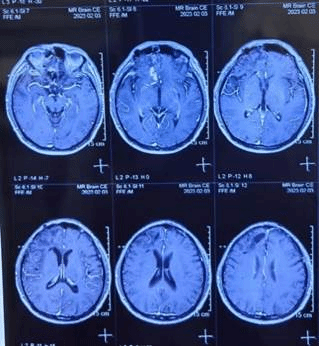

脑脓肿形成时CT(图5)脑脓肿形成时磁共振(图6)

患者术后症状改善2天后再次加重,复查CT和磁共振提示脑脓肿形成(见图5、图6)。术后第5天,在神经外科沈红教授指导下,神经外科刘利教授和殷一博主治医师为患者行机器人辅助下脓肿穿刺抽吸和Ommaya囊置入手术,术中共抽出紫褐色脓液35ml(见图7)。